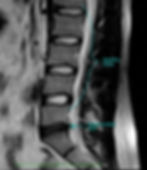

Figure 3. (Click image to enlarge.)

For some people, this deterioration, often referred to as degenerative disc disease (DDD), may lead to pain, spinal instability and other symptoms. While DDD can happen anywhere along the spine, it frequently occurs in the lower portion of the back—the lumbar spine. In the event that the disc itself is the source of pain, the patient is diagnosed with discogenic low back pain (dLBP).

The cause of dLBP may be directly related to wear and/or injury sustained by the innermost part of the disc, the nucleus pulposus (NP). This damage can be due to excessive wear and tear from poor biomechanics or as the result of any significant accident or injury. Research indicates that genetics, smoking and obesity may contribute to disc degeneration as well. The damaged disc may lead to inflammation within the NP and micro-tearing of the annulus fibrosus (AF) of the disc, the portion that surrounds and contains the nucleus.

The nucleus tissue has poor blood supply and inflammation takes very long to resolve—if it can be resolved. Compounding the situation is that sensitive nerve endings[ML1] [AM2] can grow into these microtears and render the disc hypersensitive to movements that would not typically cause pain. Other spinal elements, such as ligaments or even adjacent vertebrae, may be affected as degeneration progresses.

It is important to note that although degenerative changes may be observed, the pain may be unremarkable. Conversely, imaging may reveal very mild degenerative changes, yet the patient may be experiencing significant pain.